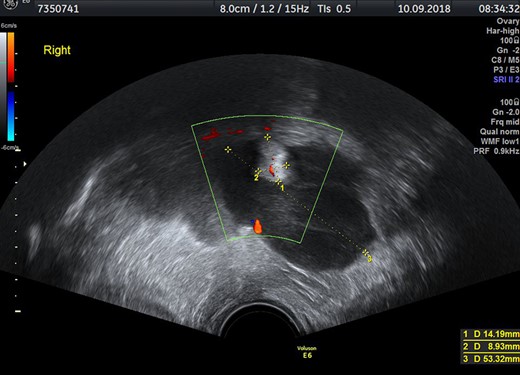

First seen by gynecologists, endovaginal ultrasound showed a solid tumor measuring 10×5×6.5 cm3, with inhomogeneous structure, suspicious of ovarian tumor (Fig. 1). Tumor markers for ovarian carcinoma were inconspicuous, only the CA 125 was slightly elevated (49.2 U/ml, reference <35 U/ml). A diagnostic laparoscopy and ovarectomy were planned.

Transvaginal ultrasound with inhomogenous mass in the right part of the small pelvis.